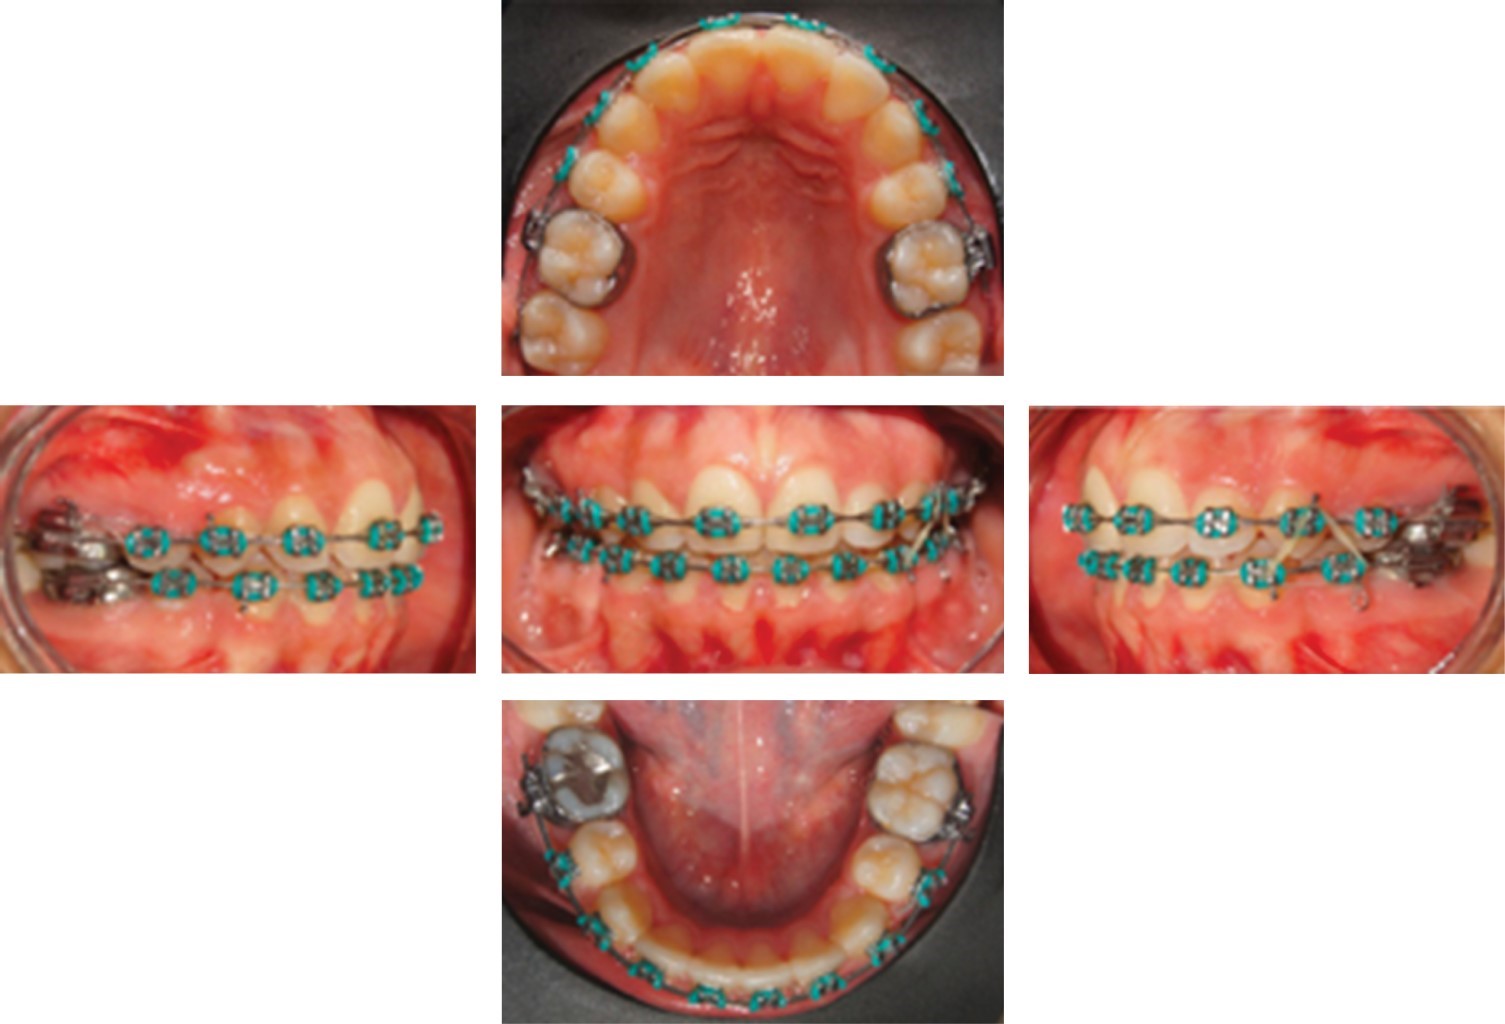

El cierre del lado derecho se realizó con un arco de cierre con loop 0.017" × 0.025", ya que con el tie back activo tuvimos problemas para efectuar el cierre. Se colocaron desoclusores posteriores para destrabar la oclusión. Mes con mes se fue activando el loop hasta completar el cierre como se muestra en la Figura 4.

Después de que se logró el cierre del espacio faltante, se retiraron los desoclusores posteriores y se realizó stripping interdentario con lija entre los órganos dentarios #15 y #13; esto para lograr conseguir un mejor engrane del canino en clase I. Durante tres meses se hizo este procedimiento para después colocar un elástico intermaxilar con vector de clase II de ese mismo lado. En la fase de terminado se colocaron elásticos verticales para así finalizar con el tratamiento como se muestra en la Figura 5.

Figura 4

Figura 5